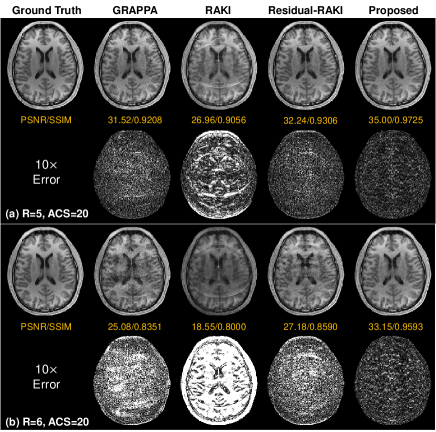

Refer to caption

Fig. 2: Comparisons between GRAPPA [2], RAKI [7], Residual-RAKI [8], and the proposed method on the 32-channel brain dataset.

Fig. 2 shows the reconstruction results on the 32-channel brain data with only 20 ACS lines. The proposed method produces improved results visually. In contrast, GRAPPA, RAKI, and Residual-RAKI suffer from artifacts and noise. Quantitatively, the proposed method achieves the highest PSNR of 35.00 dB at R=5 and 33.15 dB at R=6 and the highest SSIM of 0.9725 at R=5 and 0.9593 at R=6. Fig. 3 plots the performance variation of these methods as a function of the number of ACS lines. The proposed method is more robust to the ACS size and outperforms the compared methods, particularly at smaller ACS sizes.